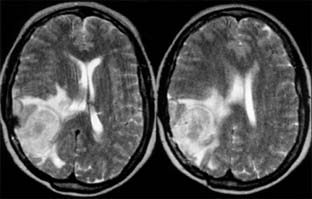

Chapter 14: Neuro-ophthalmology THE RETROCHIASMATIC VISUAL PATHWAYS Cerebrovascular disease and tumors are responsible for most lesions of the retrochiasmatic visual pathways, though almost any intracranial disease process can involve these structures. Retrochiasmatic visual field defects are homonymous. Partial lesions in the optic tract and lateral geniculate nucleus produce incongruous (or dissimilar) visual field defects due to a 90-degree medial rotation of axons in each tract and the decussation of half of the axons through the chiasm. Thus, there may be more involvement of a nasal hemifield than of its corresponding temporal hemifield. Once the lesion becomes complete, however, incongruity cannot be assessed, and this sign loses its localizing ability. Retrochiasmatic visual field defects should spare visual acuity since the visual pathway from the other hemibrain is intact. The optic tracts and lateral geniculate nucleus are infrequently affected. After several weeks to months, the disks may appear pale, and the retinal nerve fiber layer is deficient. The optic tract and lateral geniculate nucleus have at least a dual blood supply, so that primary vascular lesions are uncommon. Most cases are due to trauma, tumors, arteriovenous malformations, abscesses, and demyelinating diseases. Lesions involving the geniculocalcarine pathway to the occipital cortex produce homonymous field defects but do not result in optic atrophy (due to the synapse at the geniculate nucleus). Generally, the more posterior a lesion is located, the more congruous the homonymous visual field defect. The inferior geniculocalcarine pathway passes through the temporal lobe and the superior pathway through the parietal lobe, with macular function between them. Lesions of the inferior pathway result in superior visual field defects. Processes affecting the anterior and midtemporal lobes are commonly neoplastic; posterior temporal lobe and parietal processes can be either vascular or neoplastic. An insidious onset with mild and multiple neurologic deficits would be more typically neoplastic, whereas an acute cataclysmic neurologic event would be more typically vascular. Vascular lesions of the occipital lobe, on the other hand, are common and account for over 80% of cases of isolated homonymous visual field loss in patients over age 50 years. The most posterior tip of each occipital lobe projects to homonymous macular fields. Anterior to the macular representation lies the peripheral field; thus, vascular occlusions can selectively involve the posterior occipital cortex and produce homonymous defects with congruous macular scotomas or spare the posterior cortex, and homonymous defects with macular sparing will result. The cortical centers involved in the generation of optokinetic nystagmus lie in the area between the occipital and temporal lobes and in the posterior parietal area, which are within the vascular territory of the middle cerebral artery. Optokinetic nystagmus asymmetry characteristically occurs in parietal lesions but not in occipital lesions. An asymmetric optokinetic nystagmus combined with an occipital visual field defect indicates a process not respecting vascular territories and thus suggests a tumor (Cogan's sign). CT scans and MRI demonstrate cerebral lesions with remarkable clarity ( PREVIOUS | NEXT Page: 1 | 2 | 3 | 4 | 5 | 6 | 7 | 8 | 9 | 10 | 11 | 12 | 13 | 14 | 15 10.1036/1535-8860.ch14 |